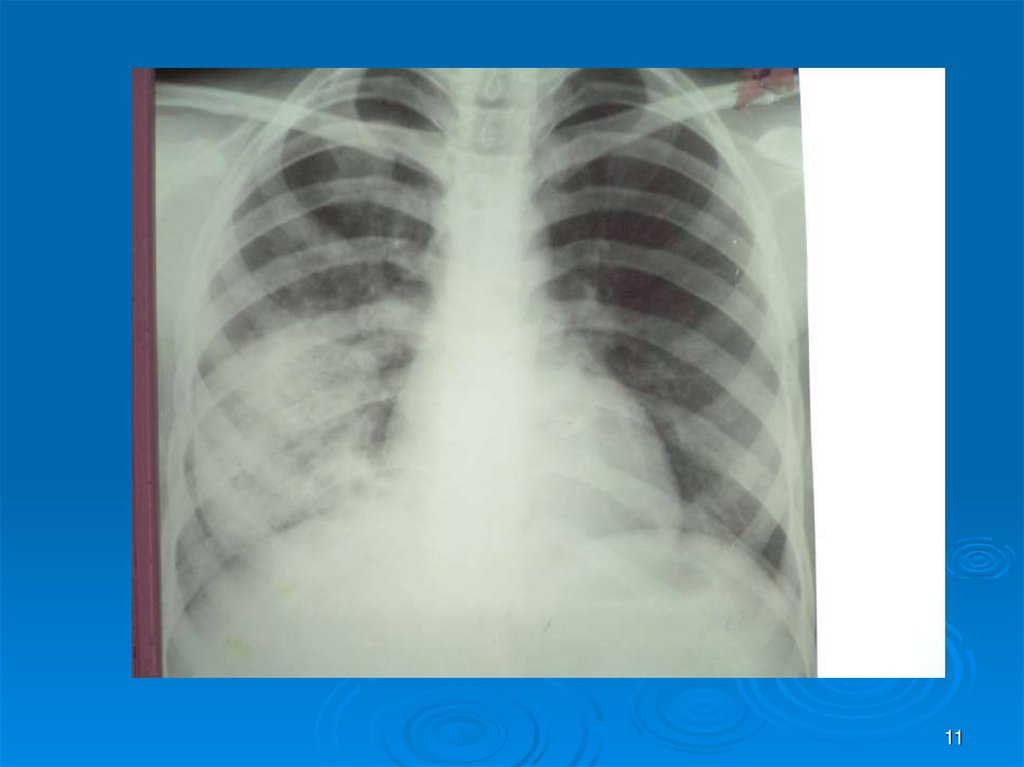

11.

11